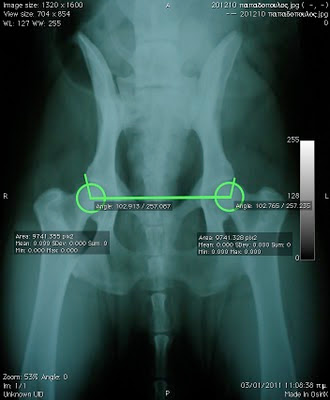

εικόνα 2- ακτινογραφία ισχίων στην οποία έχουν υπολογιστεί ψηφιακά οι γωνίες Norberg

Με τον τρόπο αυτό λαμβάνουμε ακτινογραφήματα της λεκάνης τα οποία ελέγχουμε ως προς την ποιότητα αλλά κυρίως ως προς τη συμμετρία τους. Η μη συμμετρική απεικόνιση των δυο αρθρώσεων θα οδηγήσει σε λανθασμένα συμπεράσματα. Σε κάθε άρθρωση τελικά εκτιμάται η γωνία Norberg,η σφαιρικότητα της κεφαλής του μηριαίου, η θέση της κεφαλής του μηριαίου ως προς το ραχιαίο χείλος της κοτύλης, το εύρος του μεσάρθριου διαστήματος, η πάχυνση και παρουσία οστεοφύτων στο πρόσθιο προβολικό χείλος της κοτύλης, η πάχυνση και παρουσία οστεοφύτων στον αυχένα του μηριαίου και η γραμμή Morgan. Το σύνολο των παραμέτρων αυτών θα χαρακτηρίσει την ποιότητα της κάθε άρθρωσης ξεχωριστά